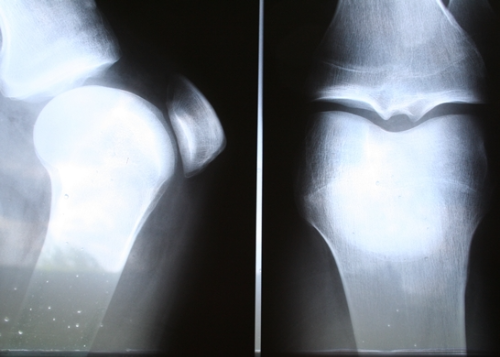

관절염은 무릎 통증의 가장 흔한 원인 중 하나입니다. 연골이 닳거나 염증이 생기면서 통증이 발생하는 질환으로, 특히 중장년층에서 많이 나타납니다.

- 퇴행성 관절염: 연골이 점진적으로 닳아 없어지면서 통증 유발